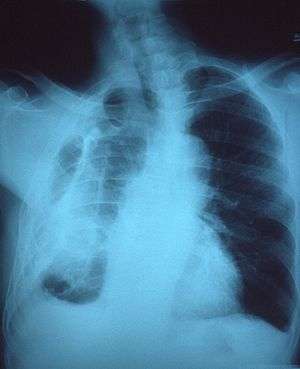

| Fibrothorax on chest x-ray | |

Pleural fibrosis & calcification. Dense pleural fibrosis with focal calcification seen here is the end result of organization of intrapleural inflammatory exudate (empyema) most likely accompanying a remote episode of pneumonia.